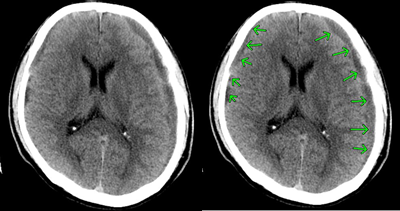

びまん性軸索損傷の具体例

症状固定段階でのT2スター強調のMRI画像です。頭頂部から頭蓋底に至る24枚のMRI画像の内の6枚目の画像です。

前頭葉、両側頭葉に黒い点がいくつか映っています。これは、脳表面の広範囲に広がる点状出血が画像として映ったものです。びまん性軸索損傷があることを示します。

点状出血を矢印で示したものが下の画像です。

被害者はフルフェイスのヘルメットを装用していました。頭蓋骨骨折や脳挫傷はありませんでした。

しかし、広範囲の点状出血に伴う軸索の損傷があります。失語、記憶、聴覚や嗅覚、言語理解、認知の領域で、脳は大部分の機能を喪失してしまいました。